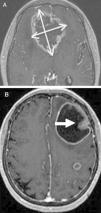

Mediante las imágenes biomédicas podemos diagnosticar, estadificar, controlar y valorar la efectividad de los procedimientos terapéuticos a los que son sometidos los pacientes oncológicos. RECIST (Response Evaluation Criteria In Solid Tumors) es el método para monitorizar el tratamiento mediante medidas unidimensionales de los tumores, obtenidas con técnicas de imagen reproducibles como son la TC, la RM y la PET. Los cambios metabólicos inducidos por los nuevos tratamientos modifican la biología y comportamiento del tumor, con discordancia ocasional entre el estado clínico del paciente y la respuesta medida con RECIST, lo que apunta a la necesidad de incluir pruebas funcionales en la valoración de la respuesta al tratamiento.

Biomedical imaging makes it possible not only to diagnose and stage cancer, but also to follow up patients and evaluate the response to treatment. RECIST (Response Evaluation Criteria In Solid Tumors) provides a method to monitor the response to treatment based on one dimensional measurements of tumors obtained with reproducible imaging techniques like CT, MRI, and PET. The metabolic changes induced by new treatments modify the biology and behavior of the tumor; occasionally, there is a discrepancy between the patient's clinical condition and the response measured by RECIST, which indicates that functional tests need to be included in the evaluation of the response to treatment.